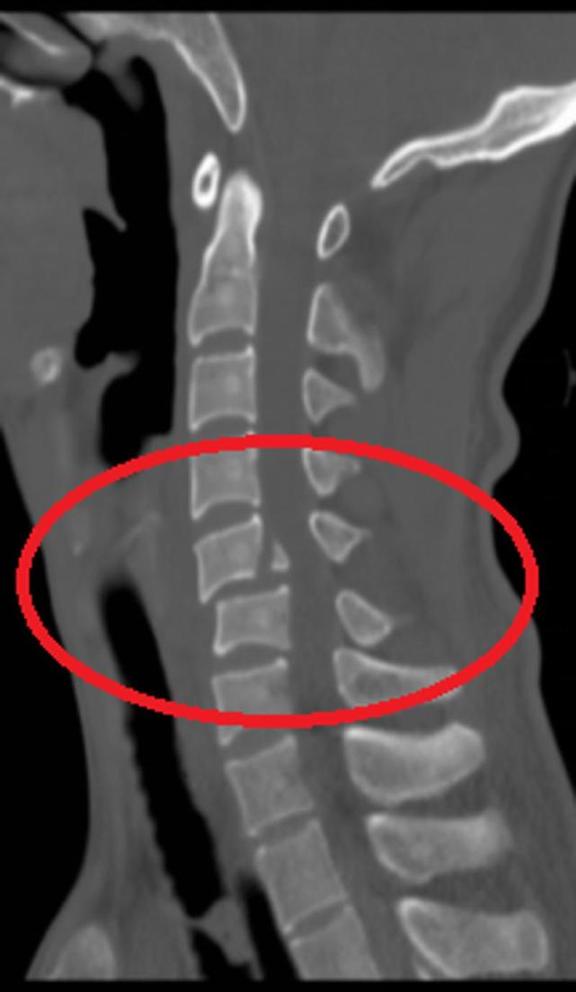

对患者的愈后,桑宏勋教授十分满意。他表示,“早期激素冲击保护脊髓、尽早制动、尽早颅骨牵引复位、及时手术十分重要,术后早期康复治疗也非常必要,多学科合作联合作战已经是目前临床治疗的发展趋势。”(记者 向雨航 通讯员 王小欢)